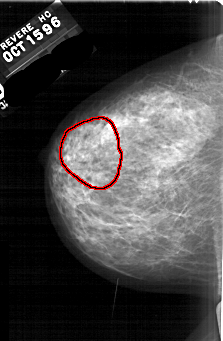

A_1668_1.LEFT_CC

LEFT_CC LINES 5791 PIXELS_PER_LINE 3781 BITS_PER_PIXEL 12 RESOLUTION 43.5 OVERLAY

FILE: A_1668_1.LEFT_CC.OVERLAY

TOTAL_ABNORMALITIES 1

ABNORMALITY 1

LESION_TYPE CALCIFICATION TYPE PLEOMORPHIC DISTRIBUTION SEGMENTAL

ASSESSMENT 4

SUBTLETY 3

PATHOLOGY MALIGNANT

TOTAL_OUTLINES 1

BOUNDARY